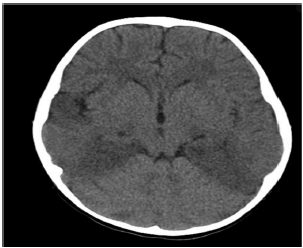

Paciente do sexo masculino de 47 anos dá entrada no pronto-socorro com quadro de febre alta de até 40 graus, há 3 dias, seguido por confusão mental e alterações de comportamento há 1 dia.

Familiares referem que o paciente em questão começou a esmurrar a parede sem propósito, além de ficar se encarando no espelho durante horas a fio.

Ao exame neurológico, agitado, Glasgow 14, sem déficits focais, mas com discurso desconexo. Realizada TC de crânio:

Realizado, ainda, exame de líquor, com os seguintes achados: glicose 55, proteínas 70, células 52 (predomínio linfo-mono), bacterioscópio negativo.

A conduta adequada para o manejo desta condição é